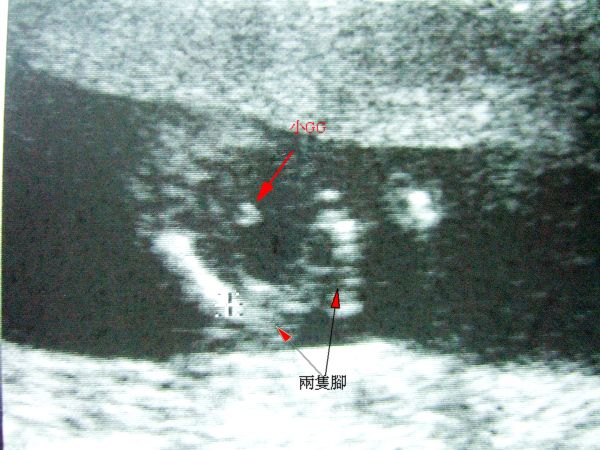

今天又去婦產科報到了

其實前兩週已經有開始感到稍稍的胎動

之前都以為這是錯覺

直到反覆的肚子有如小小電流經過一樣